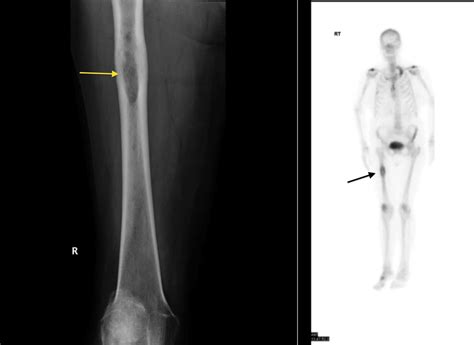

Bony lesions refer to any abnormal growths, defects, or changes in the bone tissue. These lesions can be benign (non-cancerous) or malignant (cancerous) and can occur in any part of the skeletal system. They are often detected through imaging techniques such as X-rays, CT scans, MRI, or bone scans. The characteristics of bony lesions can vary widely, making accurate diagnosis essential for appropriate treatment.

• Imaging Studies: X-rays, CT scans, MRI, and bone scans are commonly used to visualize the lesion and determine its characteristics.